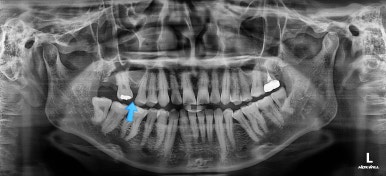

제일 하단의 X-ray에서 문제점이 보이는데요.

해당 부분의 어금니가 1개가 없었어요.

치아가 없는 자리에 바로 임플란트가 불가능합니다.

치아를 뽑자마자 임플란트를 했다면 치료는 간단했겠지만 이번의 경우는 시간이 오래 지나서 뒤쪽 어금니가 발치된 자리로 쓰러졌어요.

앞쪽 치열들도 발치된 자리로 조금씩 이동하는 바람에 틈새가 듬성듬성 생겼어요.

경우에 따라서는 맞물리는 치아(이번 환자분 경우 아랫니)가 솟구쳐 오르면서 어금니 교합이 망가져요.